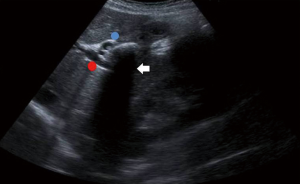

The impacted calculus along with the inflammatory response causes the external bile duct obstruction, and eventually the mucosa will erode progressing into a cholecystocholedochal or cholecystohepatic fistula that presents different degrees of communication between the bile duct and gallbladder (1,2,6,7,10,15,18-20,26). Ultrasound of Mirizzi syndrome in Figure 1. Anatomic variations of the cystic duct, represented in Figure 2, are common and predispose to the development of this syndrome, it occurs in 18–23% of cases (1,3,11,16). The distortion of the anatomy and the presence of a cholecystocholedochal fistula, increases the risk of bile duct injury during cholecystectomy (10), in Table 2 the variety of anatomical features found in Mirizzi syndrome is summarized (2,16).